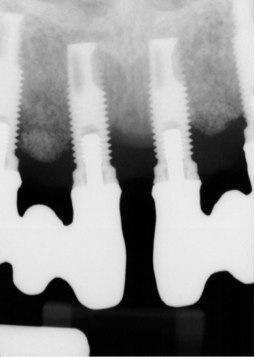

According to the European Association for Osseointegration's third Consensus Conference in 2012, 63% of patients with implants experience peri-implant mucositis, and one in five of these patients will develop peri-implantitis within 5 years of placement.2 Peri-implantitis is an inflammatory condition that develops as a response to bacteria lingering around the neck of the implant. Froum and Rosen defined peri-implantitis as peri-implant disease that has progressed beyond gingivitis or peri-implant mucositis to the point of bone loss.3 This bone loss is best identified on periapical radiographs, where the crestal bone and implant threads are clearly visualized (Figure 1). Oftentimes, computed tomography (CT) scans produce scatter radiation that can interfere with clear identification of bone loss at the neck of the implant.

(1.) Periapical x-ray image showing clear demarcation of implant threads and visible bone loss characteristic of peri-implantitis.

Figure 1